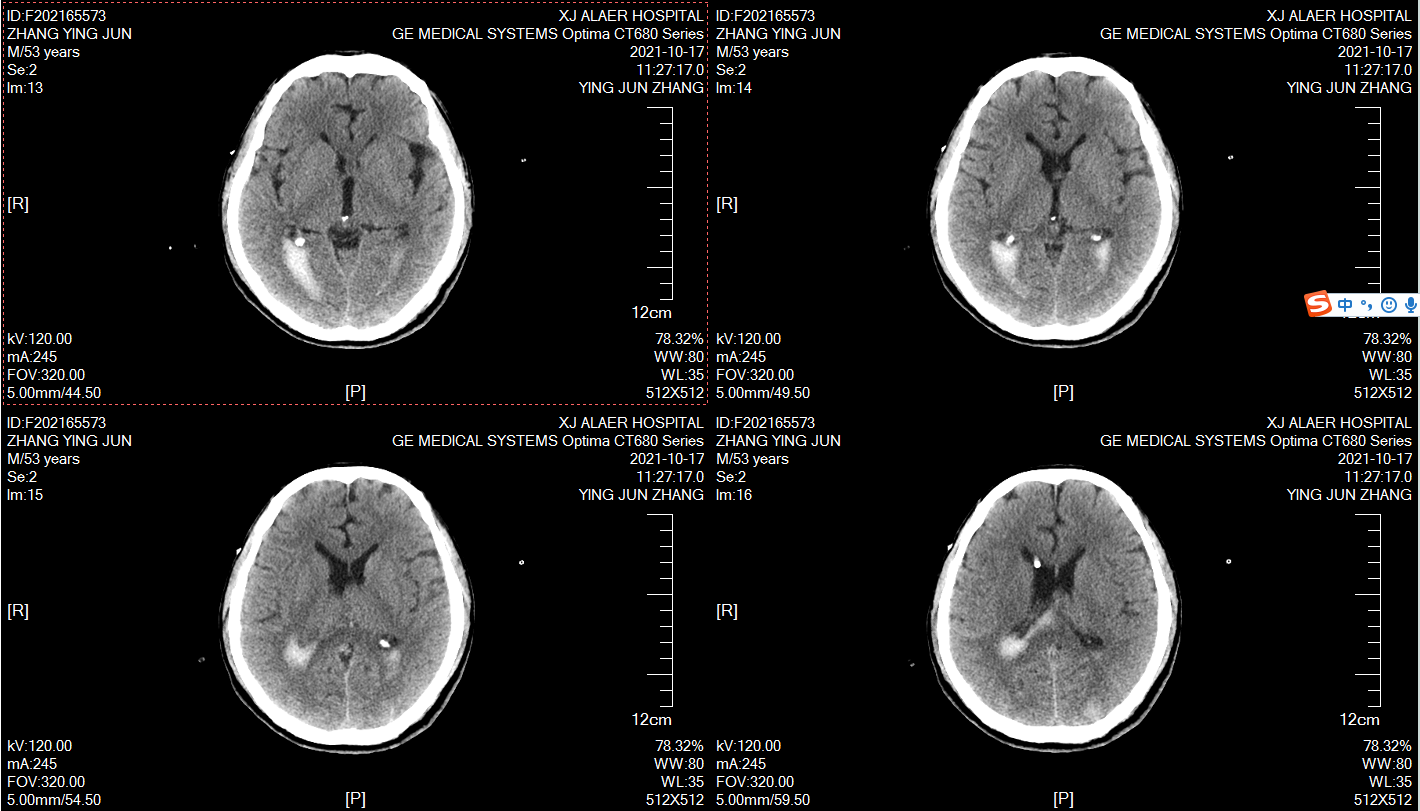

术后9天效果,夹闭24小时压力无明显变化,拔引流管!